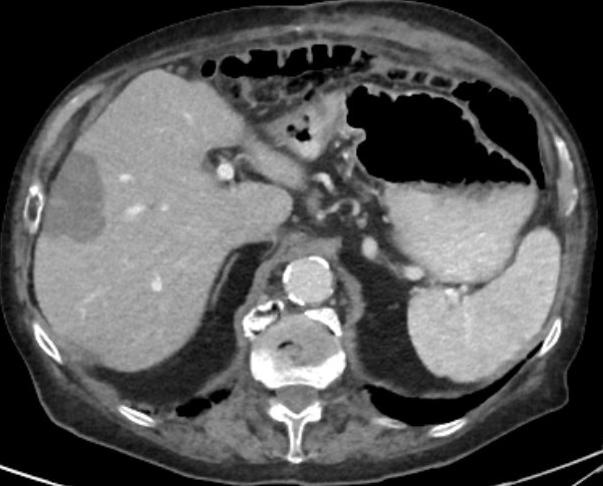

Fotos: 83jähriger Patient mit Hemikolektomie links wegen eines Adenokarzinoms der linken Kolonflexur. Nach einem Jahr Auftreten einer solitären Lebermetastase. Tumorboardbeschluss einer CT-gesteuerten Mikrowellenablation der Lebermetastase.